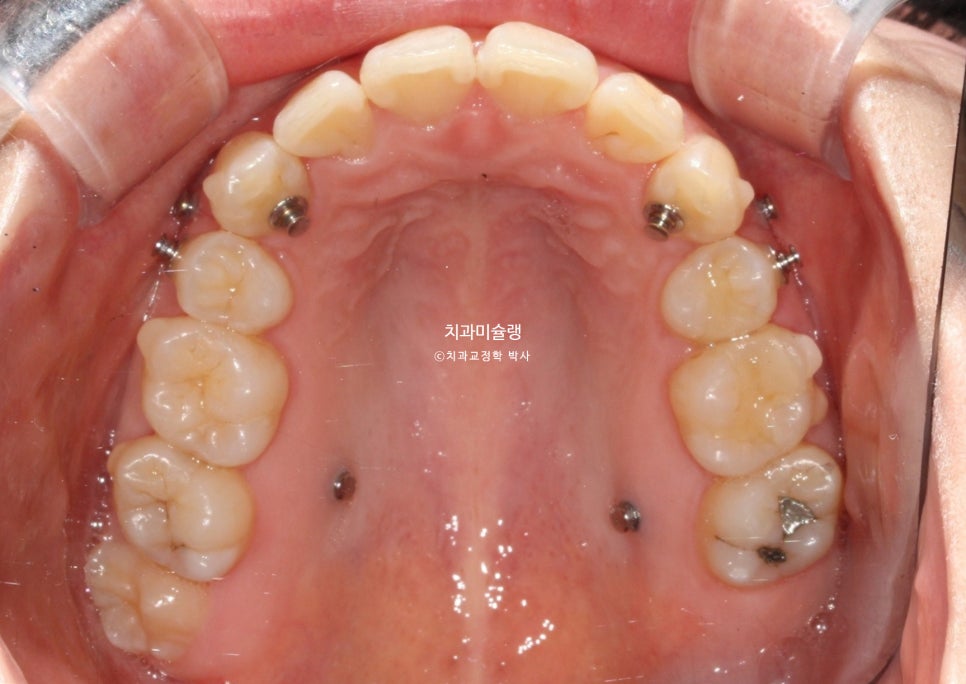

추가장치 제작에 들어갔고 19개 장치를 모두 낀 후 모습입니다.

과개교합은 잘 개선되었으나 중심선이 아직 약간 아쉽습니다.

어금니 사이사이 치실이 상대적으로 타이트하게 들어가지 않는 부분이 있어 마지막 재제작을 한번 하기로 합니다.

어금니 교합은 물샐틈 없는 1급 교합관계를 보입니다.